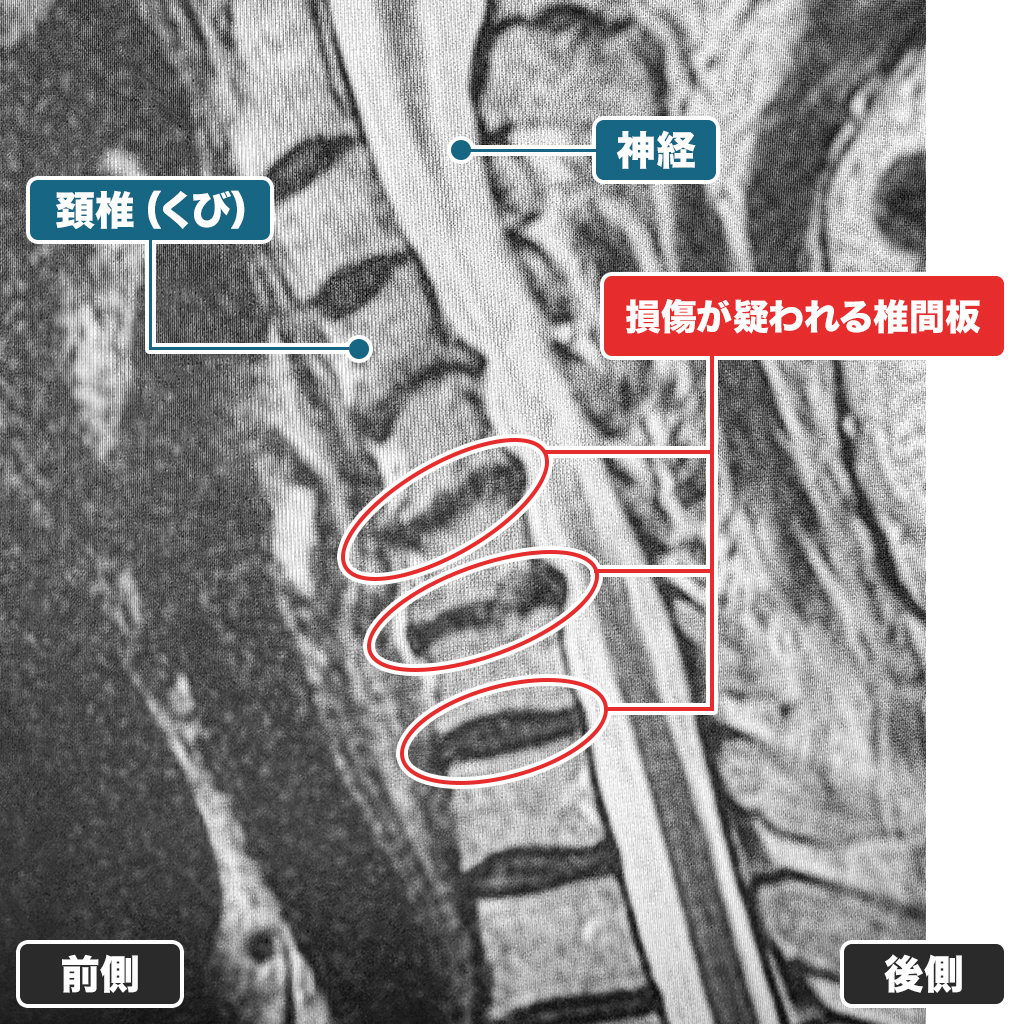

MRI検査です。C4/5、C5/6、C6/7に存在する椎間板に変形が見られます。容量も減少気味でありヘルニアも認めます。頚椎椎間板変性症と判断しました。頚部から肩甲骨にかけての疼痛原因となります。